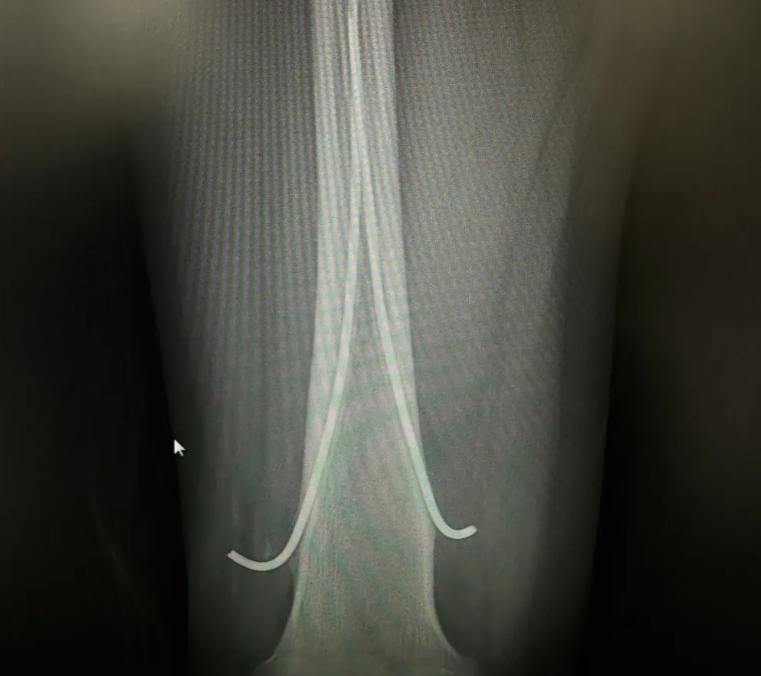

活久见:3岁股骨弹性髓内钉15年后的样子!